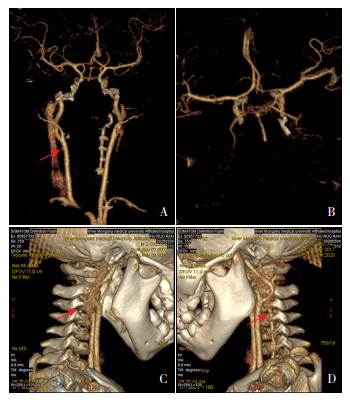

实验室检查:头部MRI示T1WI相延髓右侧背外侧低信号,T2WI相延髓右侧背外侧高信号,弥散加权成像上病变呈低信号,增强扫描病变无强化,呈低信号,提示软化灶(图 1)。头部CTA示头臂干、左侧颈总动脉及锁骨下动脉起源无异常;椎动脉左优势型,右侧椎动脉纤细,断续显示,右侧椎动脉V4段近端部分未显示,远端部分显影,考虑基底动脉盗血所致(图 2)。血常规、全血细胞形态、红细胞沉降率、肝肾功能、心肌酶、铜蓝蛋白、血氨、乳酸、血糖、甲状腺功能、狼疮全套、抗中性粒细胞胞浆抗体(ANCA)、凝血功能无异常。脑脊液常规及生化无异常,血清及脑脊液抗中枢神经系统水通道蛋白4(AQP4)抗体、抗髓鞘少突胶质细胞糖蛋白(MOG)抗体、免疫性脑炎相关抗体、寡克隆带均阴性。视频脑电图、双下肢肌电图、心脏彩超、腹部彩超、四肢动静脉彩超、颈椎+胸椎MRI平扫增强、头部MRA+MRV无异常。

图 2 头部CTA检查 图A为右侧椎动脉V4段未显影(箭头所示), 提示椎动脉V4段血管闭塞,导致延髓背外侧缺血梗死后软化;图B为基底动脉、Willis环及左右大脑中动脉正常显影;图C为右侧V4段椎动脉未显影(箭头所示),提示椎动脉V4段血管闭塞,导致延髓背外侧缺血梗死后软化;图D为左侧椎动脉正常显影(箭头所示)。 |

入当地医院后患儿病情进行性加重,给予肠内营养、头部亚低温、甘露醇降颅压、丙种球蛋白封闭抗体、低分子肝素钠改善局部循环,病情好转,但仍残留声音嘶哑、患侧共济失调、Horner综合征等表现,为求进一步治疗转入我院。入我院后头部MRI提示延髓右侧背外侧梗死后软化灶;头部CTA提示椎动脉左优势型。开始给予高压氧、局部神经肌肉电刺激、针灸、推拿对症治疗促进局部脑功能恢复。患儿声音嘶哑逐渐恢复,可与母亲正常交流,仅残留患侧共济失调、Horner综合征,嘱其规律于我院儿科门诊行功能康复治疗。患儿自发病起一直存在右侧球结膜充血症状。

3 诊断思维该患儿病例特点:(1)2岁幼儿期男童,急性起病。(2)以右侧眼睑下垂、运动倒退起病,同时伴有构音障碍,吞咽困难、饮水呛咳,哭闹时左眼有泪、右眼无泪,向右侧摔倒。(3)体检示右肩下垂,向左侧转头无力,左侧头部有汗,右侧头面部无汗,右侧眼球外展活动可,右侧眼睑下垂最严重时遮盖眼球5~7点位置,右侧结膜略充血,双侧瞳孔大小不等,左侧3 mm,右侧2 mm,对光反射存在,咽反射减弱,悬雍垂居中,右侧肢体肌力减弱4+级,活动较左侧欠灵活,右侧腹壁反射、提睾反射、膝腱、跟腱反射减弱。(4)出生史及发育史正常。(5)头部CTA示右侧椎动脉横突孔段较左侧明显纤细,考虑左侧优势型供血,右侧椎动脉入颅后未显影,双侧后交通动脉开放;头部MRI示延髓右侧背外侧梗死后软化灶。

患儿以一侧眼睑下垂起病,起病急,伴有嗜睡,声音嘶哑,吞咽困难、饮水呛咳,构音障碍,恶心呕吐,哭闹时左眼有泪、右眼无泪,不能竖头,不能独站,不能独走,向右侧摔倒,左侧头部有汗,右侧头面部无汗,右侧眼睑下垂、眼球内陷的Horner综合征表现,故排除中枢神经系统以外其他系统性疾病及周围神经病变,考虑颅内病变。考虑以下可能性:(1)颅内感染性疾病:患儿病程中有间断发热,病初伴有明显的烦躁、嗜睡,应警惕中枢神经系统感染,但患儿病程中脑膜刺激征、病理反射均阴性,脑脊液常规、脑脊液生化均未见异常,故可排除中枢神经系统感染。(2)颅内占位性病变:患儿有烦躁、恶心、呕吐等颅内压增高症状,伴有声音嘶哑、吞咽困难、饮水呛咳、构音障碍、右侧Horner综合征等颅神经受压症状,应警惕颅内占位性病变,入我院后需行头部MRI影像学检查进一步明确。(3)免疫相关性与脱髓鞘病变:患儿病程中有间断发热,伴有嗜睡、烦躁,一侧肌力下降、吞咽困难、饮水呛咳、构音障碍、共济失调等症状,但无惊厥、明显肌张力障碍、横贯性运动障碍及大小便失禁等括约肌功能障碍,无视力模糊及减退等,予检测血清及脑脊液抗AQP4抗体、抗MOG抗体、免疫性脑炎相关抗体、寡克隆带检查,均阴性,故排除免疫相关性与脱髓鞘病变。(4)先天性神经系统结构发育异常:幼儿期患儿,既往身体健康,突发一侧眼睑下垂起病,起病急,伴嗜睡、声音嘶哑、吞咽困难、饮水呛咳、构音障碍、恶心、呕吐,左侧头部有汗,右侧头面部无汗,哭闹时左眼有泪、右眼无泪,不能竖头,不能独站,不能独走,向右侧摔倒,不能排除先天发育异常。予行头部CTA,示右侧椎动脉横突孔段较左侧明显纤细,考虑左侧优势型供血,右侧椎动脉入颅后未显影,双侧后交通动脉开放,故考虑该患儿为先天右侧椎动脉发育异常引起局部缺血梗死可能性大。

4 诊断及确诊依据诊断:WS。诊断依据:(1)临床表现:①患儿有恶心呕吐、眼震等前庭神经核损害症状,②有构音障碍、吞咽困难等疑核及舌咽、迷走神经损害症状,③有病灶侧共济失调,④同侧Horner综合征;(2)辅助检查:头部MRI提示延髓右侧背外侧梗死后软化灶,头部CTA提示右侧椎动脉V4段近端部分未显影,引起延髓右侧背外侧缺血性梗死。

5 讨论WS在成人神经内科较常见,多见于高血压、高血脂、糖尿病等可引起局部栓塞的疾病[2],而在儿童中报道极少见,且大多表现不典型,临床医生经验不足,可能导致确诊困难甚至误诊。我们报道的患儿年龄2岁4个月,是迄今为止国内外儿童WS报道病例中年龄最小者,提示WS也可在幼儿期发病。WS的不同临床表现受到脑干核团和脊髓束受累的范围和严重程度的影响[2-3]。起源于椎动脉近端的穿支供应延髓后外侧,阻塞这些血管会导致延髓外侧综合征[6]。椎动脉及PICA异常为WS主要致病原因。Kim等[7]分析130例外侧髓质梗死WS患者的头部MRI及血管造影结果,发现椎动脉病变占67%,PICA病变占10%。王建等[8]分析血管变异与WS的相关性,观察组椎动脉优势及椎动脉发育不良发生率高于对照组,提示椎动脉优势、椎动脉发育不良与WS存在相关性。本例患儿为幼儿,既往无心血管基础疾病,心脏彩超未见结构及血流异常,且两次CTA结果回报均考虑左侧优势型供血,故考虑该患儿为椎动脉先天发育异常中左侧椎动脉优势型。先天性血管发育异常引起的儿童WS应受到重视,幸运的是,该患儿存在基底动脉盗血,双侧后交通动脉开放,部分补偿了右侧椎动脉血供缺失,使得右侧大脑血供可基本保证,但是却影响了延髓背外侧血供,从而导致WS。

头部MRI、CTA技术的开展在中枢神经系统疾病的诊断中发挥重要作用。在WS患者中,头部MRI较CT诊断价值更高。孙庆华等[18]对53例延髓梗死患者行头部CT检查,均未发现病灶,提示CT检查诊断WS价值较低。Ross等[19]对4例临床诊断为WS患者分别进行了头部MRI和CT检查,其中3例经头部MRI发现小脑梗死病灶,而CT并未发现病灶。胡杰等[10]研究中,36例WS患者均经头部MRI检查发现延髓背外侧梗死灶,其中22例完成头部CT检查并未发现延髓背外侧病灶。除此以外,头部CTA检查广泛应用于头颈部血管狭窄的临床评价,能清晰显示血管狭窄的部位和程度,对先天性血管结构发育异常或外伤后引起的椎动脉夹层的诊断占优势,也具有较高WS诊断价值。而本例患儿通过头部CTA、MRI准确发现异常发育血管,符合上述结论。